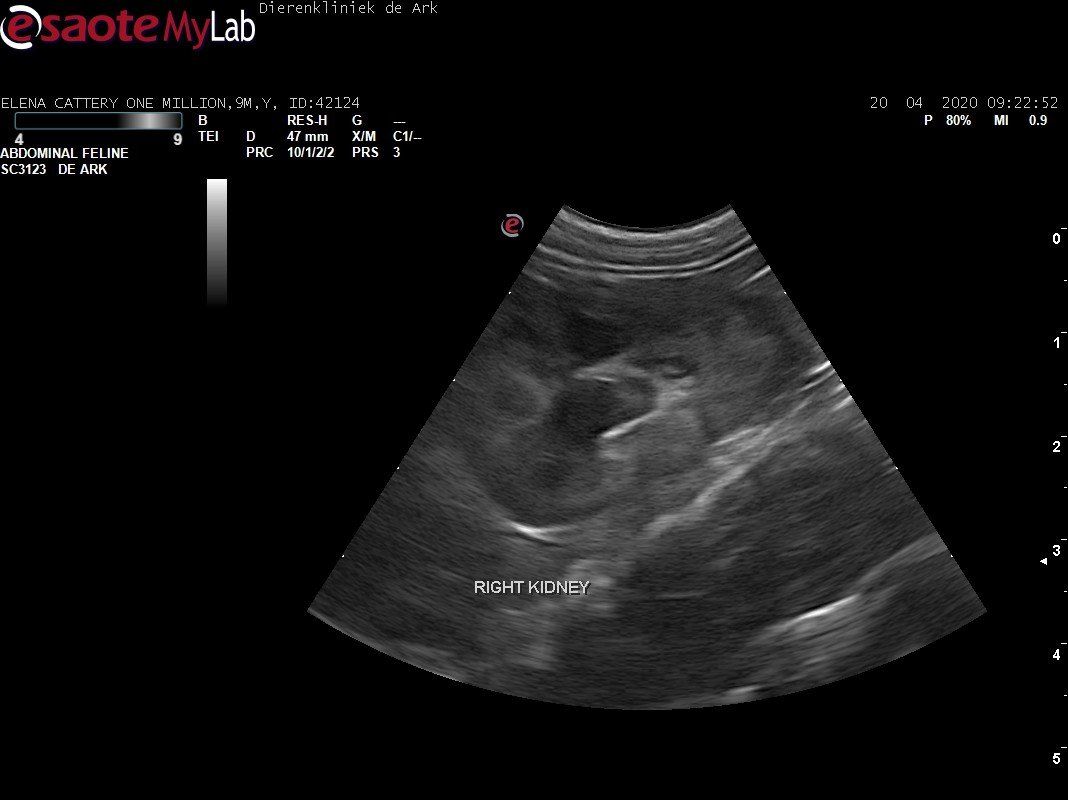

3,200 kg , echo en nieuw bloedonderzoek gedaan wat perfect ging door middel van gapabetine

Voor de garanties en om recht te hebben op medicatie bij herval eist Mutian diverse onderzoeken en controle momenten. Dit zijn bloedonderzoeken maar ook zoals hieronder te zien is echo's. Elana is volledig gecontroleerd op afwijkingen, gelukkig waren de echo's goed.